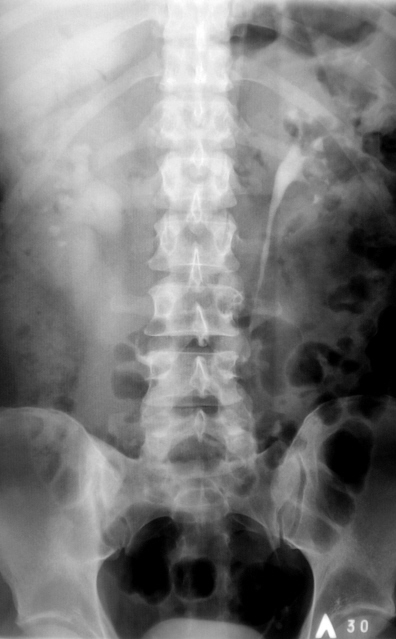

Иллюстрации 1, 2. На обзорной рентгенограмме области почек и мочевыводящих путей слева на уровне Т12 и Л1 определяются две тени характера конкрементов различных размеров значительной интенсивности неоднородной структуры.

Иллюстрация 3. Определяется ротация тела Л3. На уровне сегмента Л3 – Л4 определяется локальное окостенение передней продольной связки, по всей видимости, в результате подсвязочного костеообразования. Определяется некоторая ротация тела Л3.